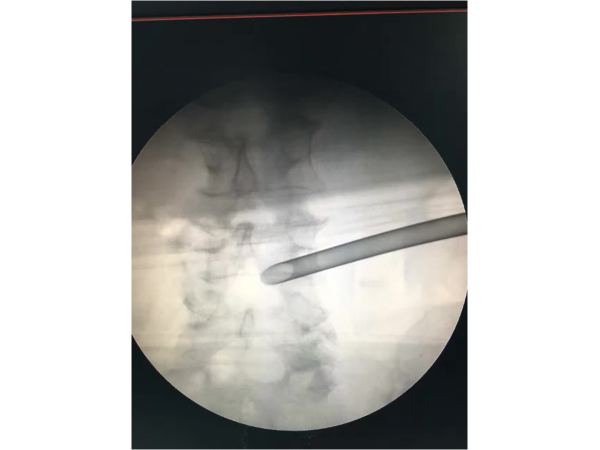

產(chǎn)品說明:1.手術(shù)體位:體位可以采用俯臥位和側(cè)臥位,我們習(xí)慣于采用俯臥位來完成PELD手術(shù)。2.畫線:先畫出腰椎棘突的連線,再畫出雙側(cè)髂嵴

產(chǎn)品說明:腰5/骶1椎間盤突出癥、側(cè)隱窩骨性狹窄。經(jīng)保守治療無效,后主管醫(yī)生陳永紅副主任醫(yī)師為患者實施局部麻醉下微創(chuàng)椎間孔鏡治療,術(shù)

產(chǎn)品說明:這是一位中年男性,有著5年頸段食道腫瘤和2年“胃造瘺術(shù)”病史的多病患者。3月前出現(xiàn)腰部、左臀部及小腿酸痛不適,癥狀逐漸加重